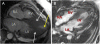

Case presentation: A 63-year-old Caucasian woman presented with a history of chest pain and shortness of breath causing significant limitations on her daily life activities. She had a history of coronary artery disease. Her physical examination was unremarkable. Transthoracic echocardiography revealed normal systolic function and significant concentric left ventricular hypertrophy that was greater in the mid-apical region. Nuclear magnetic resonance imaging confirmed significant hypertrophy of the median segments of the left ventricle. The patient had persistent symptoms despite receiving optimized medical treatment, and a surgical approach was indicated. As a myectomy using transaortic technique was thought to be difficult to perform in her case, a transapical approach was used. No complications occurred, and her symptoms resolved.